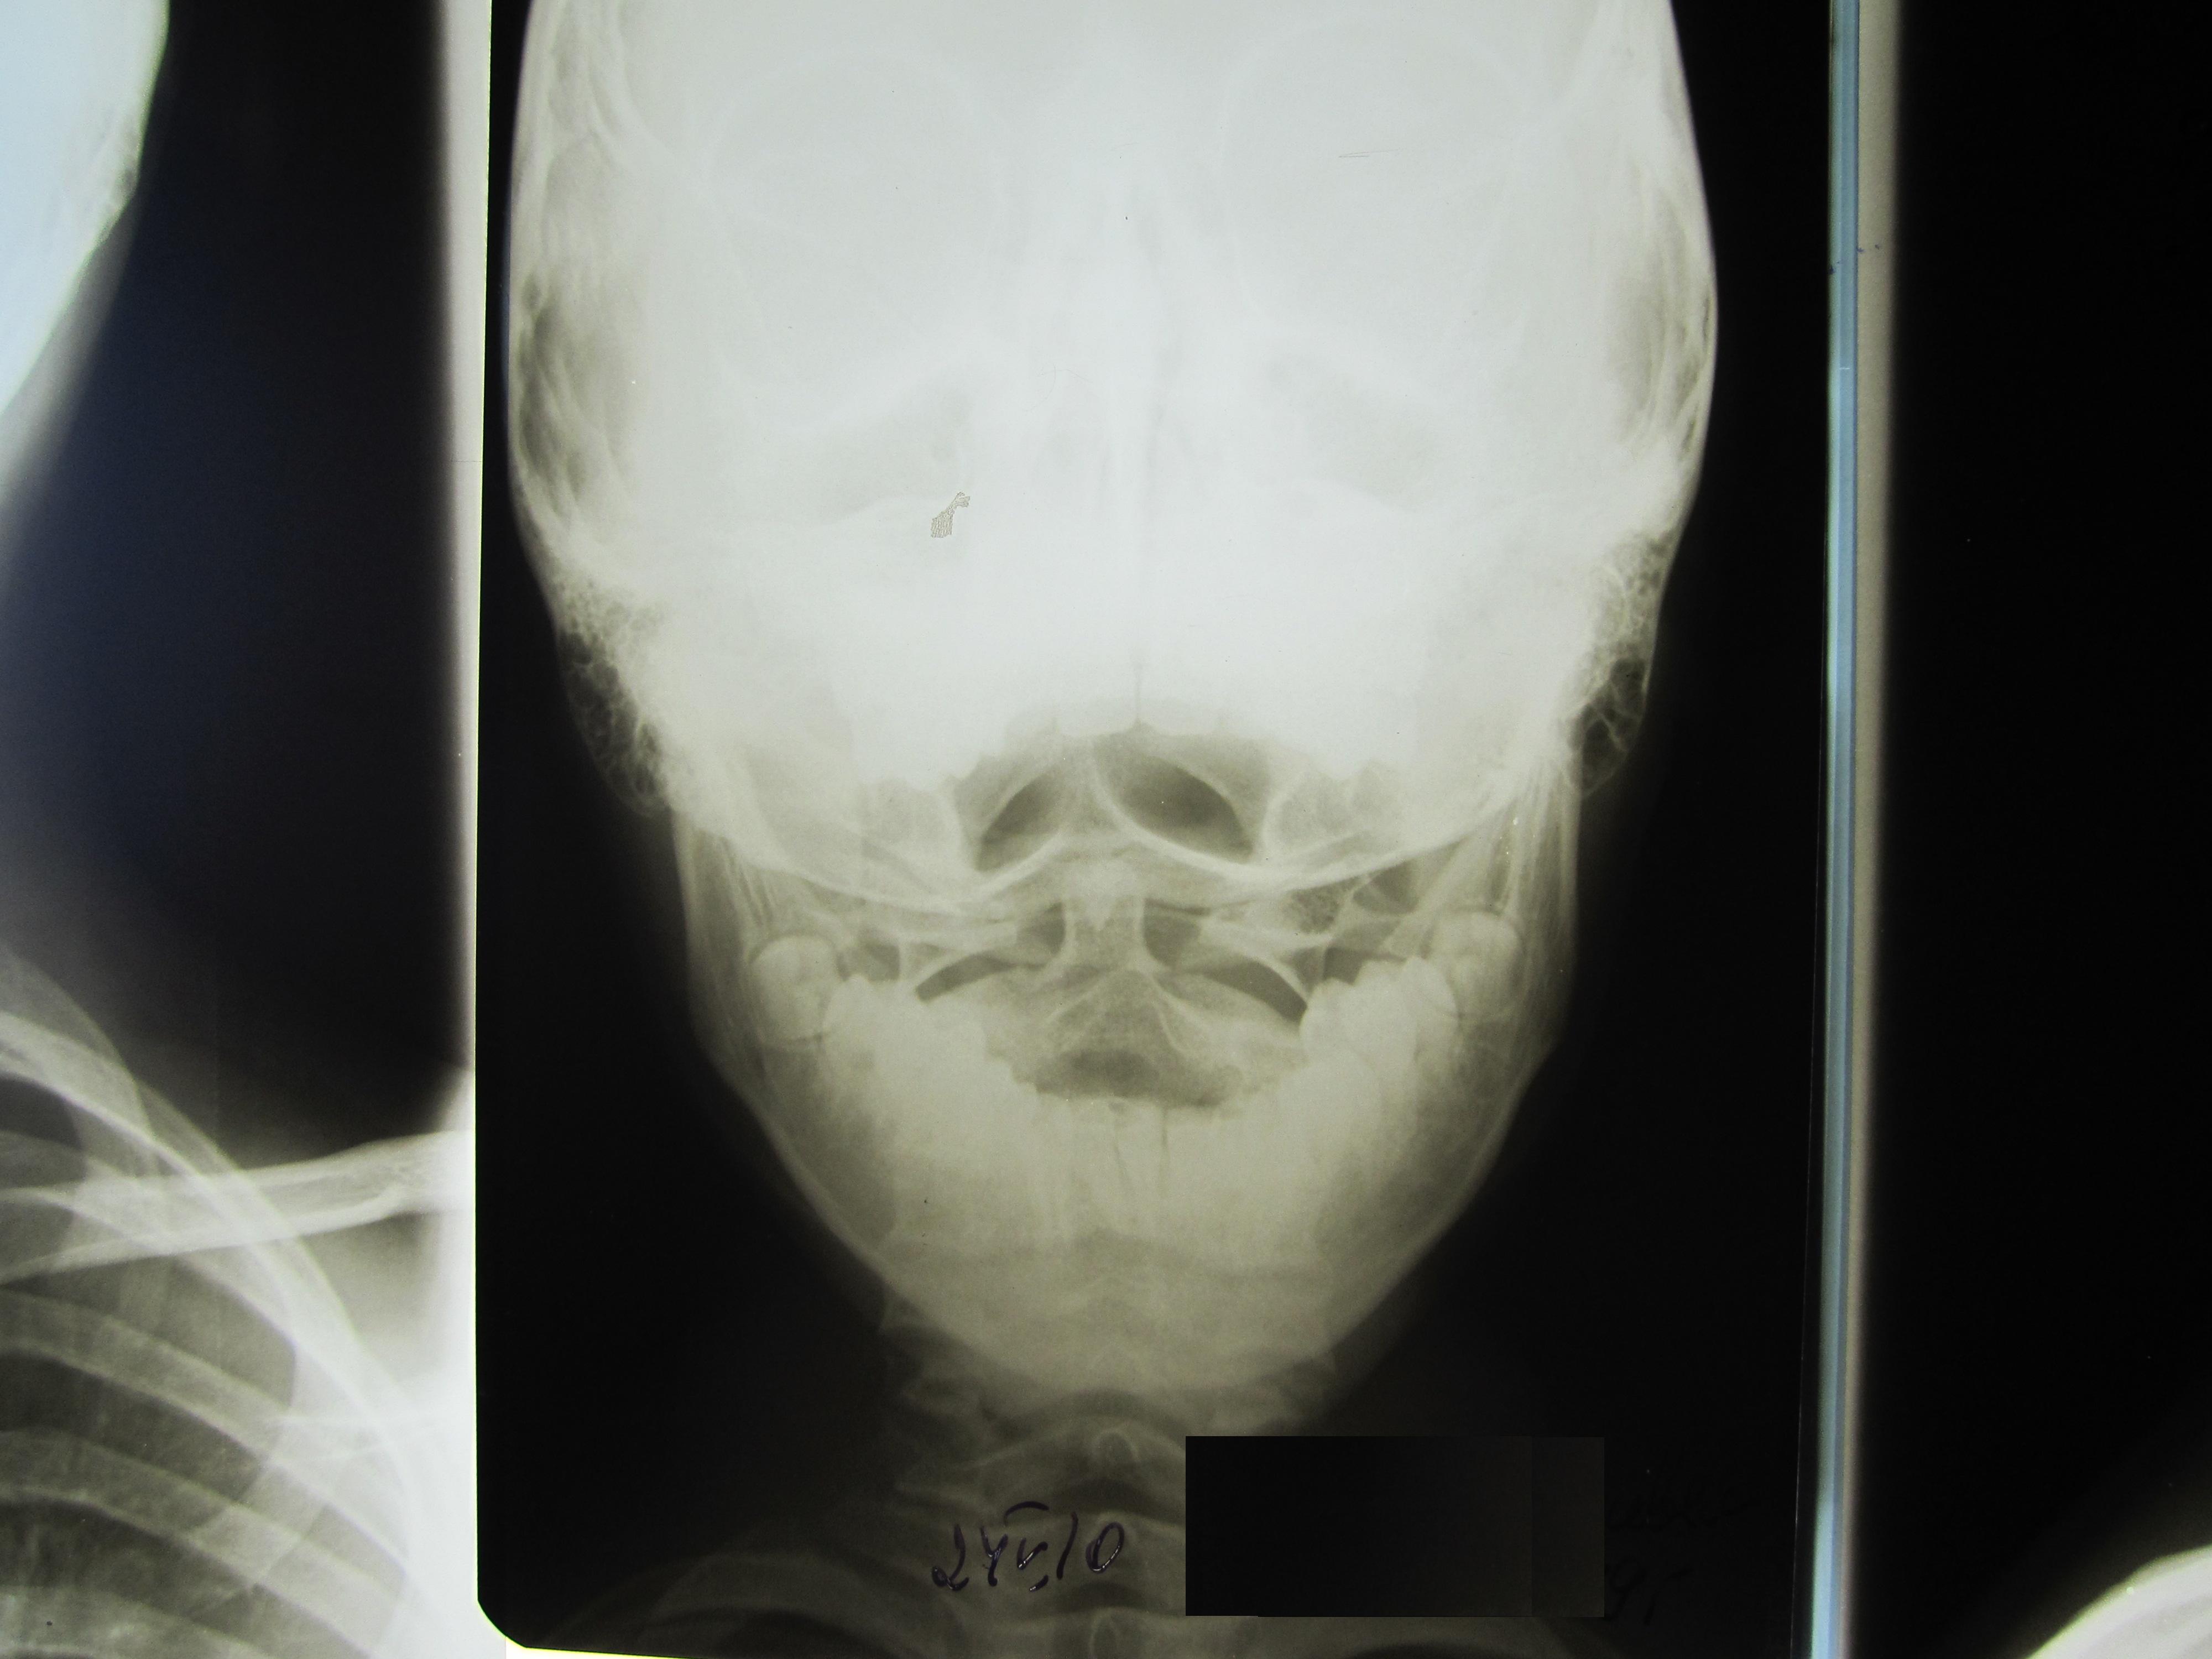

Уважаемые коллеги, здравствуйте! Посмотрите, пожалуйста снимки, интересует атланто-окципитальное сочленение в положении разгибания. Какой диагноз? Нестабильность?

Подвижность в атланто-окципитальном сочленении в норме меньше, чем здесь...

Явной аномалии не видно, наверно слабость связочного аппарата, в сочетании с избыточной нагрузкой... Дети и подростки - очень своеобразный контингент. Стоят на головах, подымают друг друга за голову, деруться...